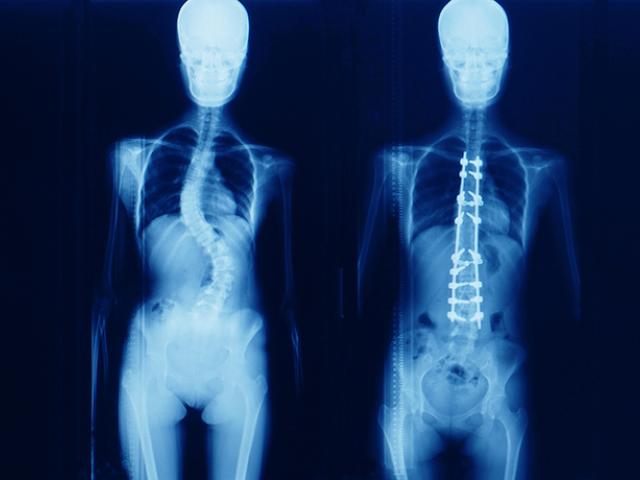

La escoliosis es una curvatura anormal de la columna vertebral

La escoliosis es una curvatura anormal de la columna vertebral hacia un lado y tiene varias causas diferentes.